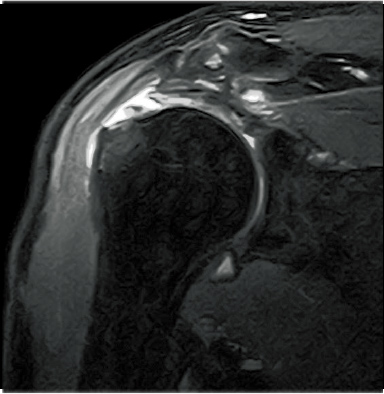

FatSat-PDWI

T2WI